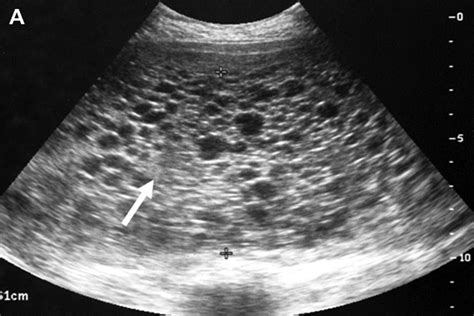

Radiologists look for specific visual markers to identify this condition. The most classic description of a molar pregnancy ultrasound image is often called the "snowstorm" appearance. This occurs because the abnormal placental tissue creates multiple echo-producing interfaces, making the interior of the uterus look like a blizzard on the screen.

Other indicators include:

• Absence of Fetal Parts: In a complete mole, there is an absolute lack of fetal tissue.

• Cystic Spaces: Large, fluid-filled cysts are often visible within the mass.

• Ovarian Cysts: It is common to see theca lutein cysts on the ovaries, caused by the high levels of human chorionic gonadotropin (hCG) hormone produced by the molar tissue.